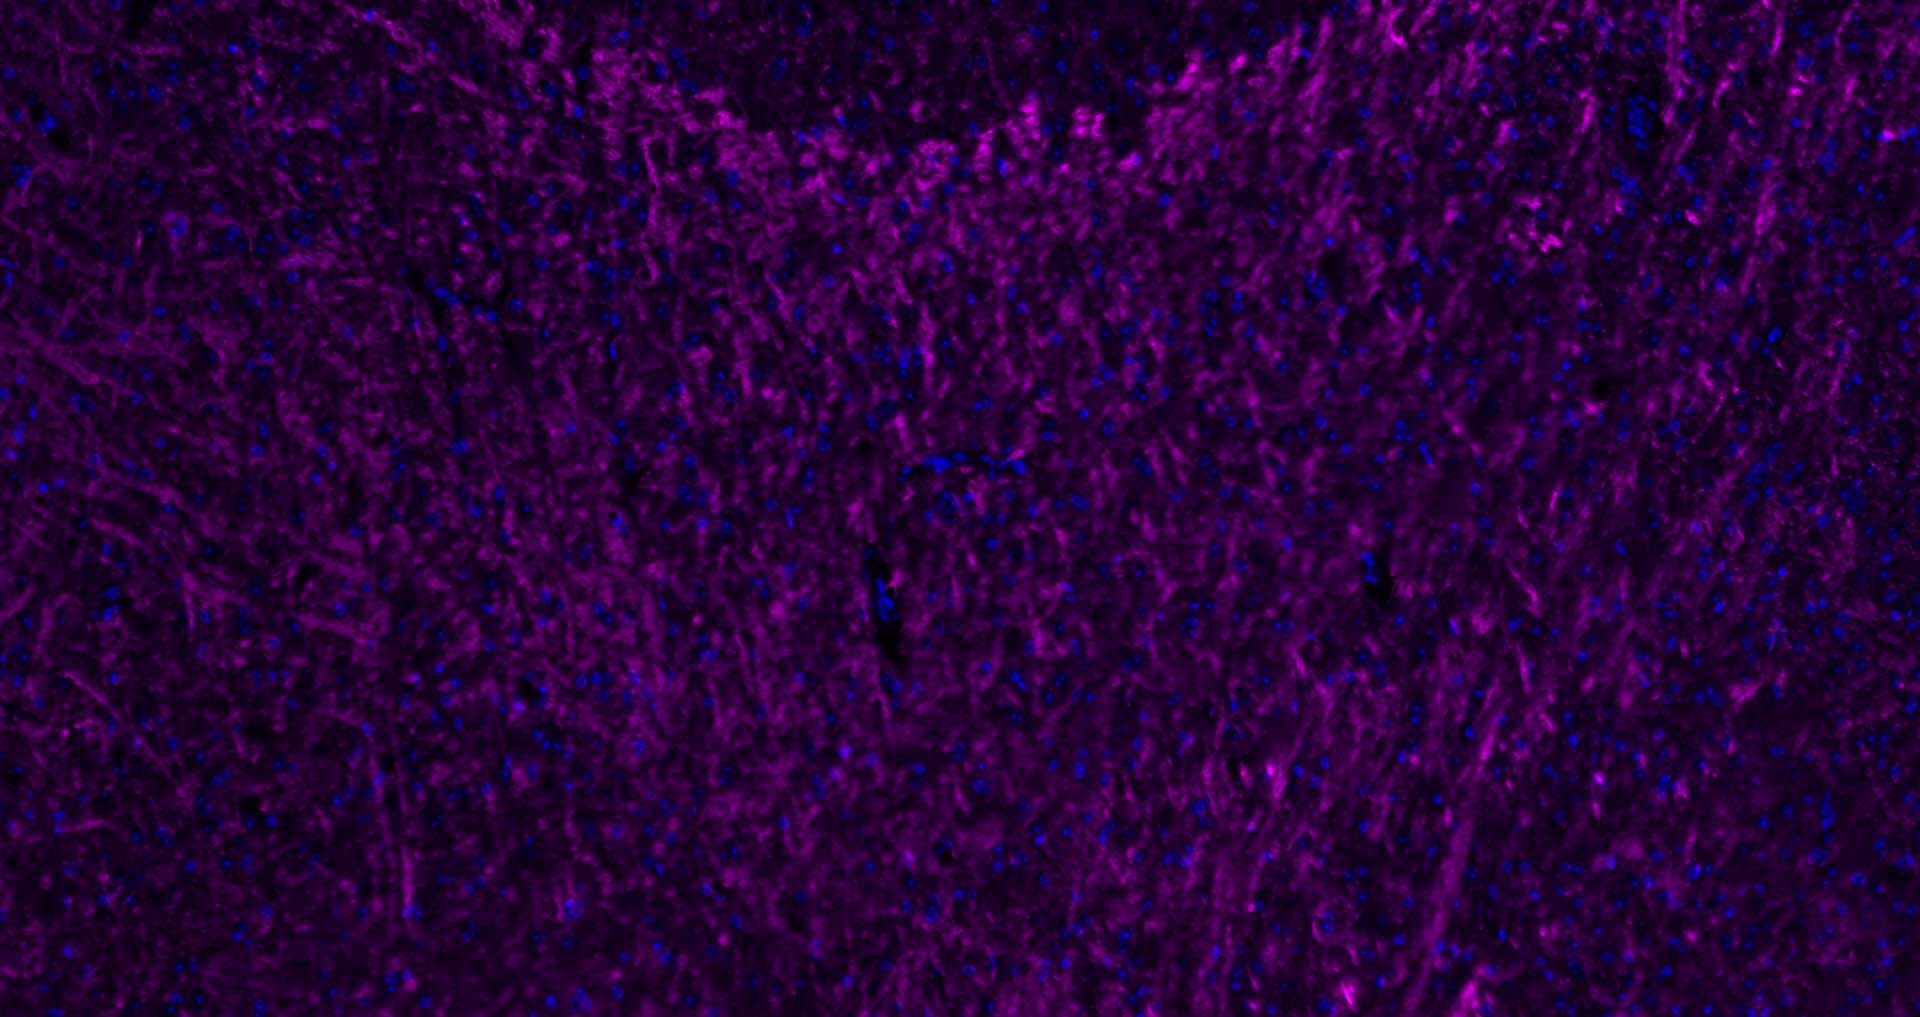

Paraformaldehyde-fixed, paraffin embedded Human Left Parietal Lobe; Antigen retrieval by boiling in sodium citrate buffer (pH6.0) for 15 min; Antibody incubation with MBP Polyclonal Antibody, Unconjugated (bs-0380R) at 1:200 overnight at 4°C. Followed by conjugated Goat Anti-Rabbit IgG antibody (Rose red, bs-0295D-Cy5), DAPI (blue, C02-04002) was used to stain the cell nuclei.

Paraformaldehyde-fixed, paraffin embedded Human Cerebellum; Antigen retrieval by boiling in sodium citrate buffer (pH6.0) for 15 min; Antibody incubation with MBP Polyclonal Antibody, Unconjugated (bs-0380R) at 1:200 overnight at 4°C. Followed by conjugated Goat Anti-Rabbit IgG antibody (Rose red, bs-0295D-Cy5), DAPI (blue, C02-04002) was used to stain the cell nuclei.

Paraformaldehyde-fixed, paraffin embedded Rat Cerebellum; Antigen retrieval by boiling in sodium citrate buffer (pH6.0) for 15 min; Antibody incubation with MBP Polyclonal Antibody, Unconjugated (bs-0380R) at 1:200 overnight at 4°C. Followed by conjugated Goat Anti-Rabbit IgG antibody (Rose red, bs-0295D-Cy5), DAPI (blue, C02-04002) was used to stain the cell nuclei.

Paraformaldehyde-fixed, paraffin embedded Mouse Cerebellum; Antigen retrieval by boiling in sodium citrate buffer (pH6.0) for 15 min; Antibody incubation with MBP Polyclonal Antibody, Unconjugated (bs-0380R) at 1:200 overnight at 4°C. Followed by conjugated Goat Anti-Rabbit IgG antibody (Rose red, bs-0295D-Cy5), DAPI (blue, C02-04002) was used to stain the cell nuclei.

Paraformaldehyde-fixed, paraffin embedded Mouse Cerebrum; Antigen retrieval by boiling in sodium citrate buffer (pH6.0) for 15 min; Antibody incubation with MBP Polyclonal Antibody, Unconjugated (bs-0380R) at 1:200 overnight at 4°C. Followed by conjugated Goat Anti-Rabbit IgG antibody (Rose red, bs-0295D-Cy5), DAPI (blue, C02-04002) was used to stain the cell nuclei.